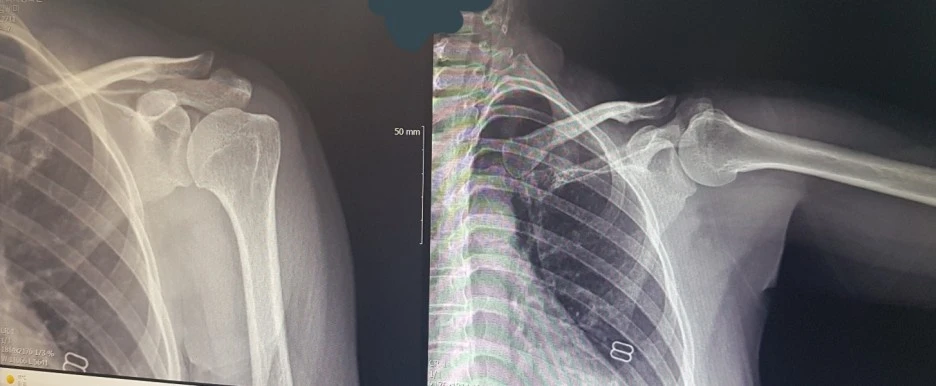

회전근개파열 엑스레이 사진

A: 어깨를 움직일 때 4가지 근육이 작용을 하거든,. 들어줄 때, 안으로 돌릴 때 바깥으로 돌릴 때 쓰이는 근육이 다 달라요. 일반적으로 회전근개라고 하는데 들어줄 때 쓰이는 근육이 문제가 생겼네

B: 팔을 올릴 때만 아팠는데 ... 그래서 그랬구나